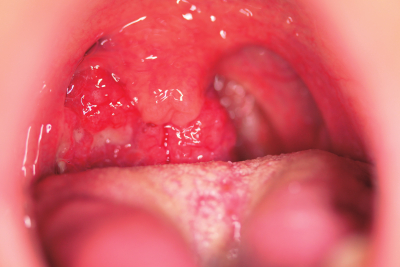

52歳の男性。咽頭痛と嚥下困難とを主訴に来院した。

咽頭所見、頭部造影MRIのT1強調水平断像及び生検組織のH-E染色標本を別に示す。生検組織の免疫組織化学染色標本で、ヒトパピローマウイルスの持続感染を示唆するp16蛋白が強陽性であった。口腔粘膜擦過検体のPCR検査でもヒトパピローマウイルスが検出された。